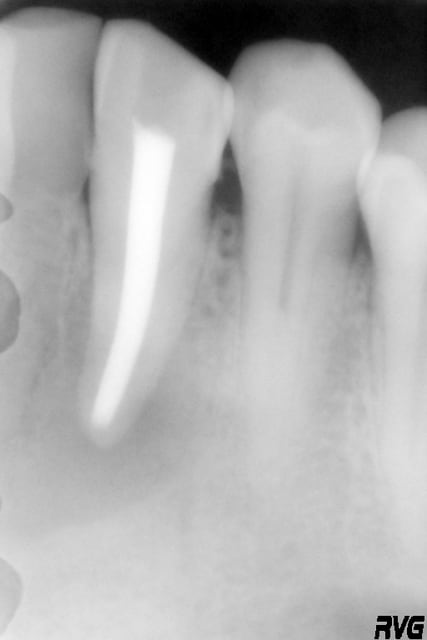

Un patient, 60 ans, présente une image apicale au niveau de 33, avec une fenestration ; tiers apical de la racine visible via la fenestration.

Ci joint, la radio de la 33 après le curetage par le stomato.

la radio pas top mais on l'a, radiologiquement correcte on dirait

Il s'agit juste d'une fenestration ou d'un apex extracortical ?